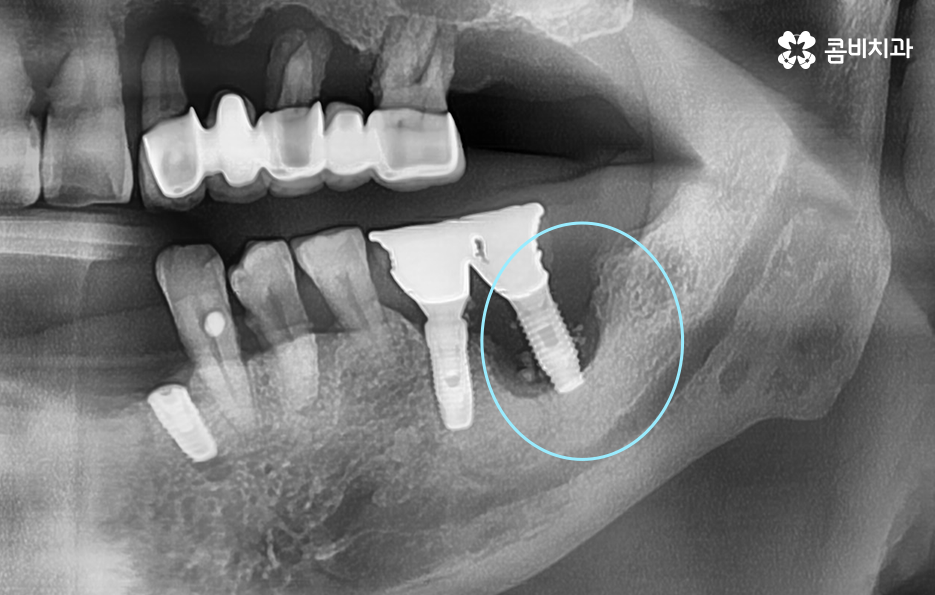

위 환자분의 케이스를 살펴보면 임플란트 시술 후 임플란트 주위염이 발생되어 이미 치조골이 상당히 녹았을 정도로 엑스레이 상에서도 관찰할 수 있어요

임플란트는 보편적으로 분리형이 주로 사용되고 있는데 임플란트의 인공치근은 잇몸 뼈와 골유착이 되어 단단하게 고정이 되어 있고 그 위에 지대주와 보철물이 연결되어 있는 형태이기 때문에 임플란투 수명에 있어서 임플란트의 인공치근 부분이 염증으로 인해 잇몸 뼈가 녹게 되면 임플란트 자체도 흔들리게 되고 결국 제거 후 재수술을 해야 될 수 있어요